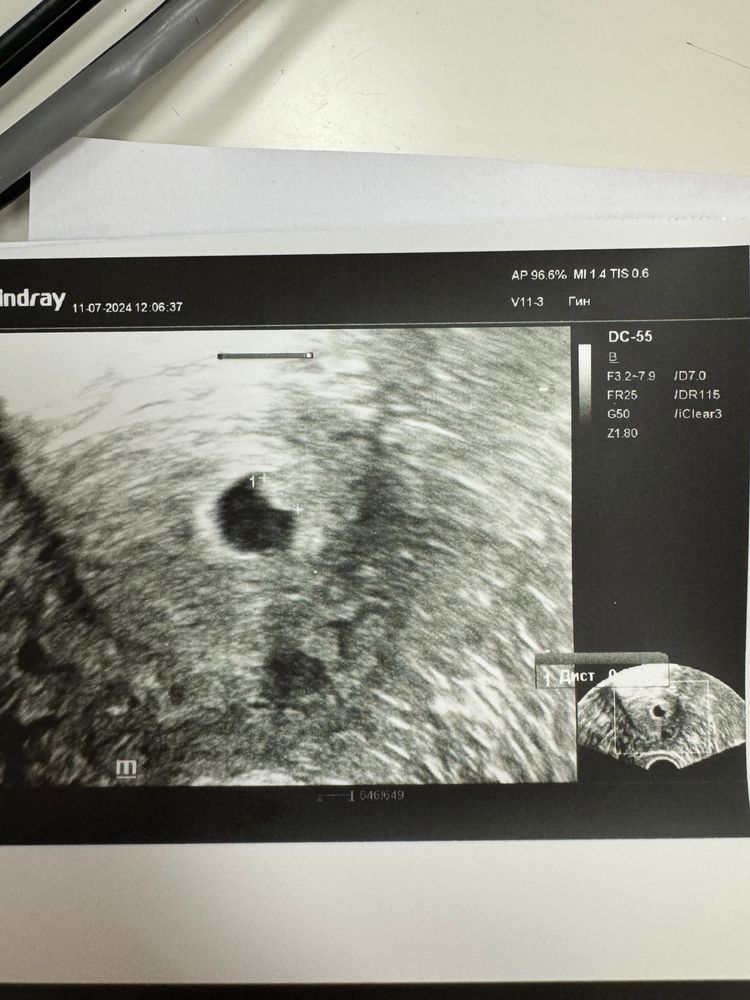

Марина, вот как то так, почему то ктр не написан Изображение

Марина, я вообще не понимаю ничего 😧 если у меня такой большой ЖМ, то почему его не видно У Вас эмбрион хорошо видно 😍

Там где стоит метка